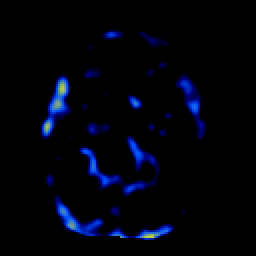

SPECT TL Study #1 -- Slice #25

[Home][Help][Clinical][Tour 1][Tour 2][Tour 3] Slice 25